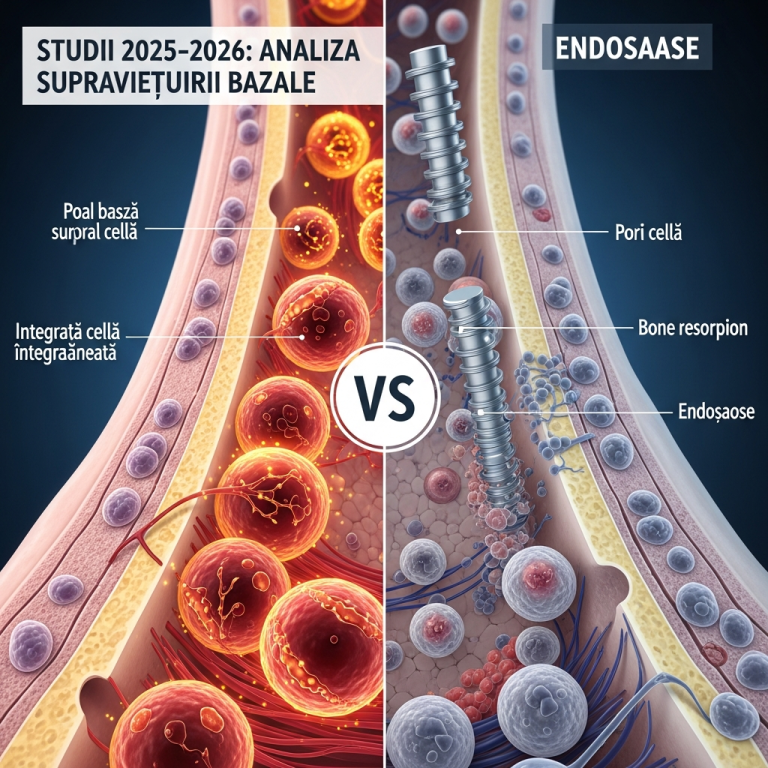

Menținerea sănătății gingiilor este fundamentală pentru succesul pe termen lung al implantelor dentare. Inflamația gingivală, sau periimplantita, reprezintă o complicație majoră care poate compromite stabilitatea osului și a implantului. Conform studiilor recente (2025–2026), prevenția eficientă se bazează pe o strategie multifactorială care începe încă din faza de planificare. Acest gid sintetizează protocoalele actuale de igienă și urmărire medicală, esențiale pentru a minimiza riscul inflamator și a asigura integritatea implantului.

Tehnologii și protocoale de diagnostic precoce

Detectarea precoce a modificărilor inflamatorii este cheia. Protocoalele din 2025–2026 includ analize fluide creviculare pentru markeri inflamatori și utilizarea laserului de diagnostic cu fluorescență pentru a identifica modificări tisulare încă de la debut.